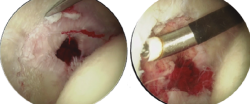

Retiraremos los osteofitos con una fresa desde la unión capsulolabral para movernos más cómodos y seguiremos con la resección del os labrale, osteofito o labrum calcificado (Figura 3).

Figura 3. Paciente con osteofito en el reborde acetabular (imagen izquierda). Resección del osteofito en el reborde acetabular (imagen derecha).